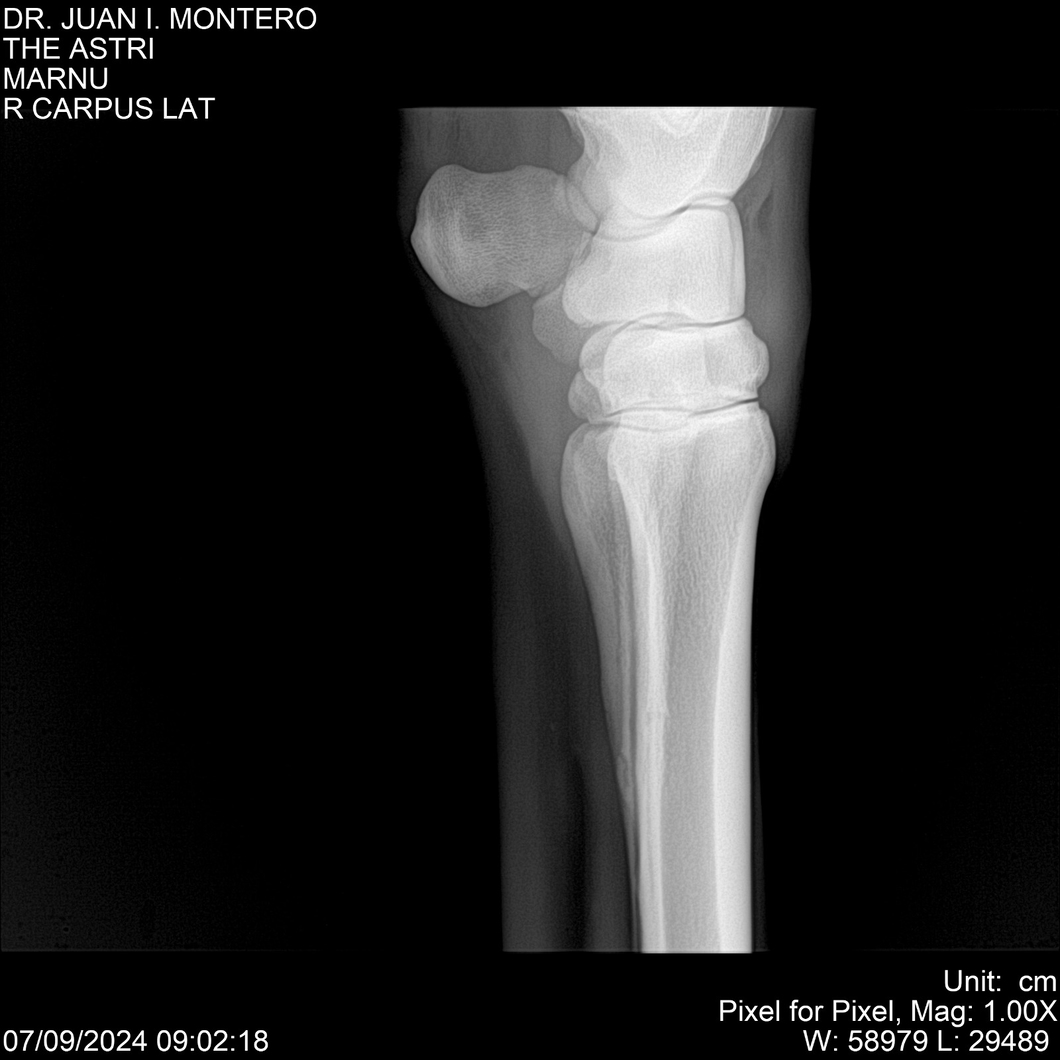

LOTE 10, THE ASTRI Lote Anterior Volver al remate Lote Siguiente Ficha Contacto Montevideo - Ficha del Lote Identificador: #282514 Categoría: Yeguarizos Montevideo - 60 Visualizaciones ClicData Contacto Empresa: Abelenda N. R., Walter Hugo Nombre*: Teléfono* : E-mail* : Mensaje Enviar Registrese gratis Este contenido Exclusivo está disponible sólo para usuarios registrados Ingresar